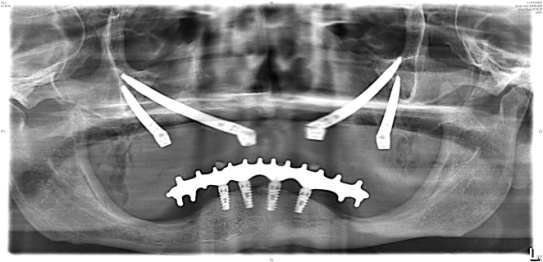

Chirurgia Oro-Mascellare per riabilitazioni protesiche post oncologiche

I pazienti che per motivi oncologici o per esito di osteonecrosi per uso di farmaci della categoria bifosfonati (in uso nelle gravi forme di osteoporosi o nel trattamento coadiuvante delle metastasi ossee)hanno subito gravi demolizioni dei mascellari e conseguente perdita della funzionalità masticatoria necessitano di ricostruzione e rifunzionalizzazione dell'apparato masticatorio con ricostruzione dell'osso mandibolare o del mascellare superiore attraverso innesti di osso , di lembi mucosi e/o muscolari di vicinanza ed a volte di implantologia preprotesica con impianti zigomatici , pterigoidei o convenzionali , tutto cio'con il fine di ripristinare una corretta funzione ma anche una auspicabile vita di relazione.

![]() | ![]() | ![]() | ![]() |